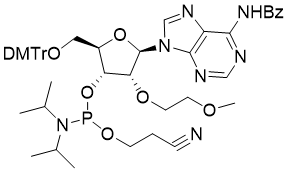

馬鞍山致研生物醫(yī)藥科技有限公司成立于馬鞍山市鄭浦港新區(qū)現(xiàn)代產(chǎn)業(yè)園。公司專(zhuān)注于生物小分子、醫(yī)藥中間體相關(guān)產(chǎn)品的研發(fā)和生產(chǎn),產(chǎn)品主要包括DNA亞磷酰胺單體、RNA亞磷酰胺單體、特殊單體以及按照客戶(hù)要求定制的RNA和DNA,并且公司提供定制合成等方面的研究服...

馬鞍山致研生物醫(yī)藥科技有限公司成立于馬鞍山市鄭浦港新區(qū)現(xiàn)代產(chǎn)業(yè)園。公司專(zhuān)注于生物小分子、醫(yī)藥中間體相關(guān)產(chǎn)品的研發(fā)和生產(chǎn),產(chǎn)品主要包括DNA亞磷酰胺單體、RNA亞磷酰胺單體、特殊單體以及按照客戶(hù)要求定制的RNA和DNA,并且公司提供定制合成等方面的研究服...